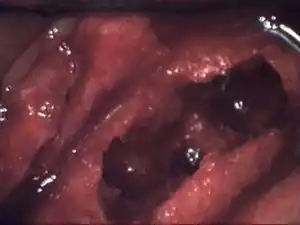

Osteonecrosis of the jaw of the upper left jaw in a patient diagnosed with chronic venous insufficiency | |